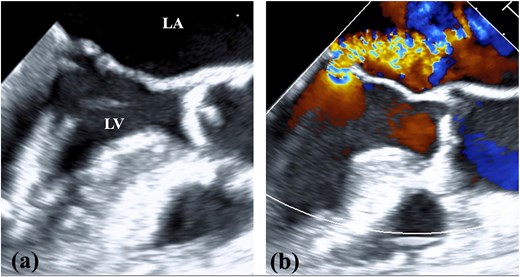

A 78-year-old woman with severe mitral regurgitation (MR), tricuspid regurgitation, and atrial fibrillation was admitted with worsening heart failure. She had hypertension, but no known CHD. She was 138 cm tall, weighing 34.6 kg, with a body mass index of 18.3 kg/m2. Her vital signs were normal. The N-terminal fragment of pro B-type natriuretic peptide was elevated at 2577 pg/mL. Chest radiography revealed cardiac enlargement and bilateral pulmonary edema. Transesophageal echocardiography (TEE) revealed shortening of the anterior and posterior leaflets of the mitral valve, with thickening of the commissure, indicating severe MR (Fig. 1 and Video 1). The tricuspid annulus diameter increased to 29.4 mm. No congenital heart diseases were detected. Contrast-enhanced computed tomography (CT) revealed that the left innominate vein coursed posterior to the ascending aorta, the so-called ALBCV, and joined the superior vena cava (SVC) 3 cm from the right atrium (Fig. 2 and Video 2). Venography of the left upper limb confirmed the ALBCV (Fig. 3 and Video 3). No communication existed between the ALBCV and the coronary sinus.

Contrast-enhanced CT. (a) The ALBCV coursed posterior to the ascending aorta. (b) The ALBCV joined the SVC at a peripheral location ⁓3 cm from the right atrium. No right aortic arch or double aortic arch was observed.